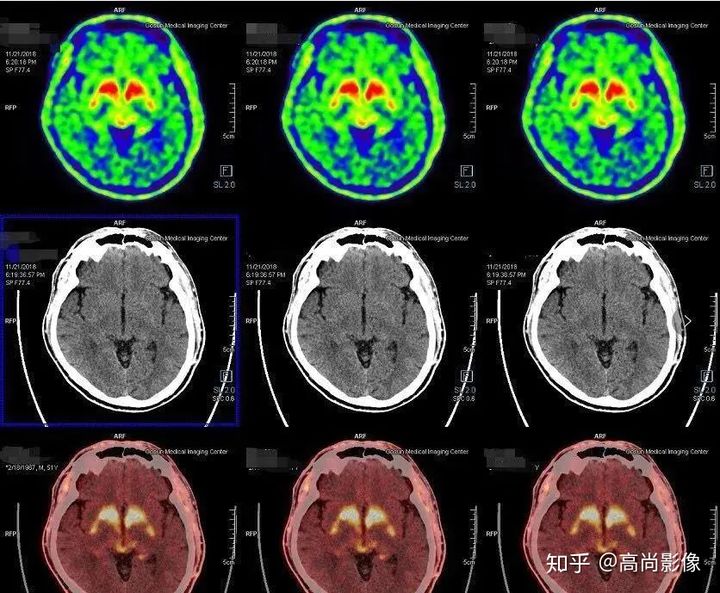

發(fā)作間期癲癇灶呈代謝減低

發(fā)作期癲癇灶呈代謝增高

雙側(cè)尾狀核、殼核多巴胺轉(zhuǎn)運體分布對稱、均勻

雙側(cè)尾狀核多巴胺轉(zhuǎn)運體分布對稱,左側(cè)殼核后部多巴胺轉(zhuǎn)運體分布較對側(cè)明顯減少,結(jié)合童大媽癥狀,先考慮帕金森。